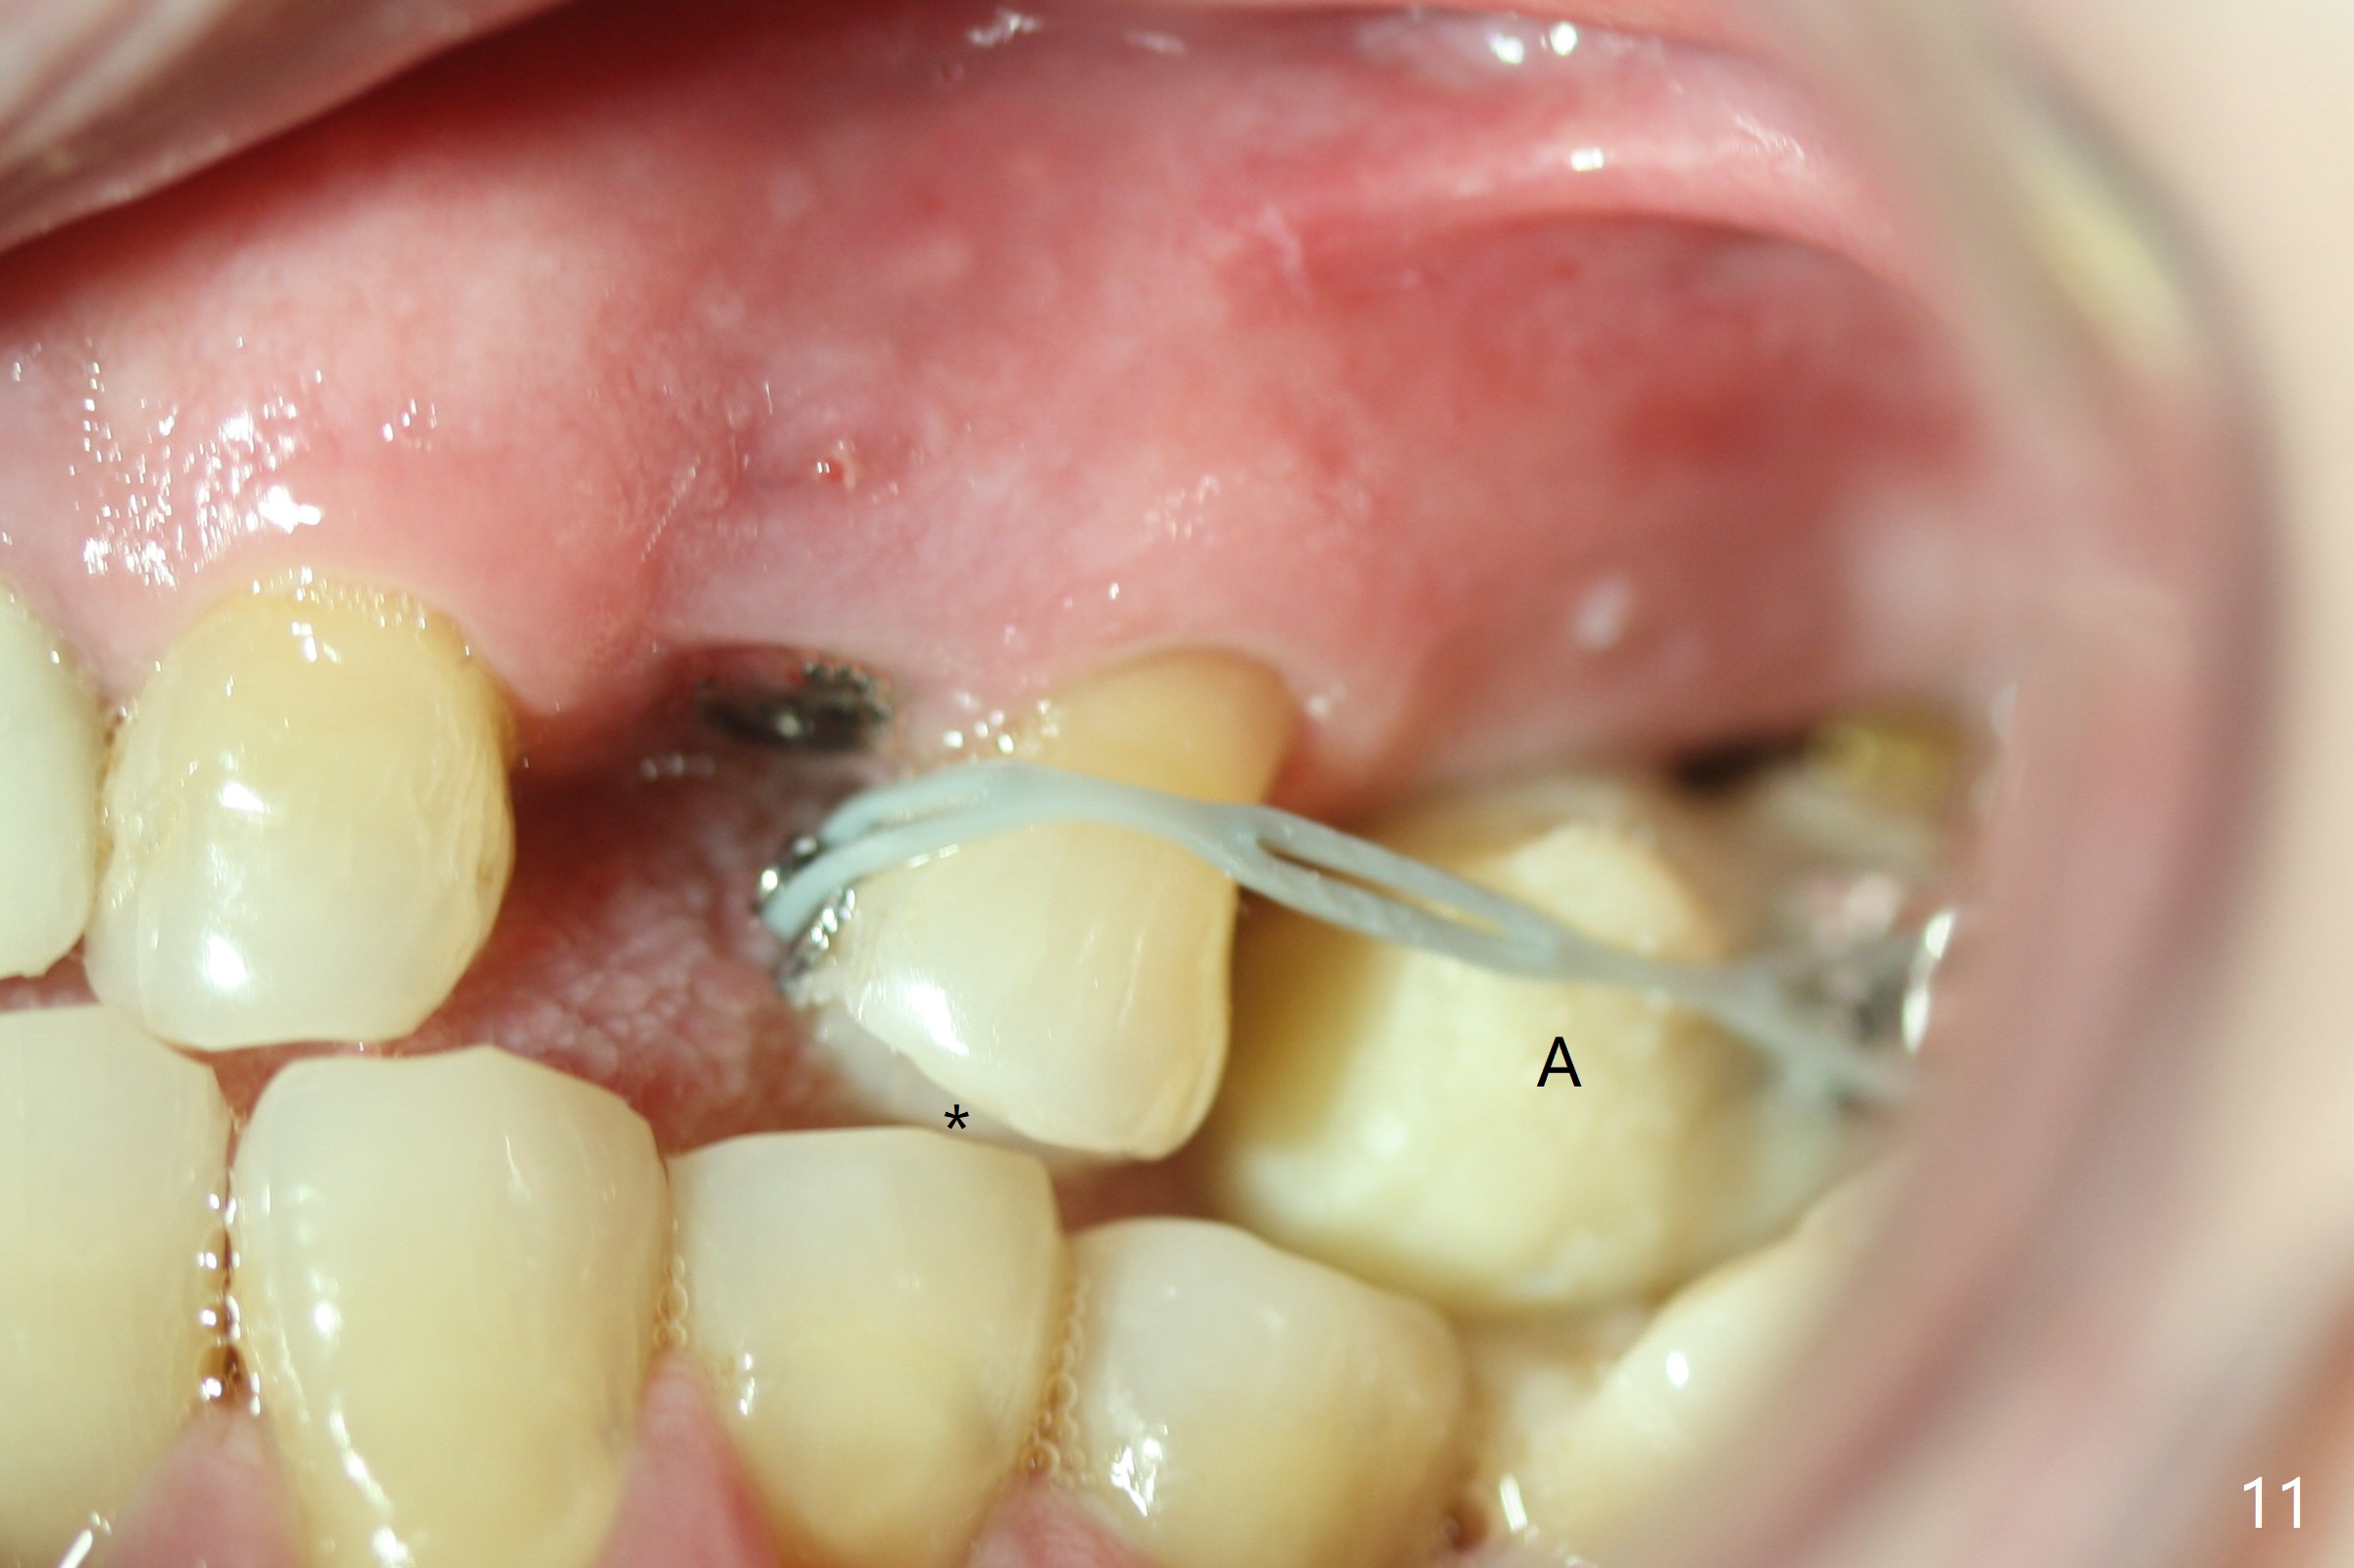

A few days prior to surgery, the tooth #12 developed abscess, self controlled by water pik (Fig.1 *). The buccal plate is defective. Initial osteotomy is close to the root of the tooth #11 (Fig.2). After adjustment of the trajectory and the depth of osteotomy (Fig.3), a 3.8x15 mm dummy implant is placed (Fig.4,5). In spite of a shorter implant (3.8x13 mm) placed deeper, approximately 7 mm implant threads are not covered buccally by the native bone (Fig.6 red dashed line). If the implant were placed deeper, the crown/implant ratio would become more unfavorable (abutment screw loosening, Fig.7). Since a mill abutment (4.5(2) mm) is inserted before Vanilla Graft, the deepest portion of the socket is unfilled (Fig.7 *). With meticulous use of a long explorer and additional allograft, the space is closed (Fig.8 *). The buccal plate collapses with apparently fistula formation 2 months postop. The patient removes the provisional for cleaning. It appears that the mill abutment is buccally placed and needs heavy reduction. The mill abutment is loose 2 months 10 days postop. When it is retightened, it tilts distal. Bone remains around the implant 6 months postop (Fig.9). Without a provisional at #12 for 5 months, the tooth #13 appears to have been shifted mesially (Fig.10 arrow). The mill abutment at #12 changes to a healing one. A lingual button is placed in the mesial surface of #13. Splinted provisional is fabricated with supraocclusion at #14 and 15 as an anchor (implants). The tooth #13 is being distalized with power chains. Limited ortho is finished nearly 2 months post banding (Fig.15,16).